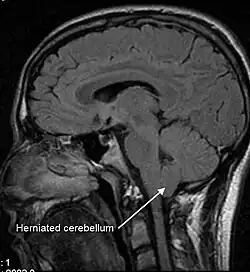

An untreated CSF leak can result in coma or death as late stage findings as the brainstem herniates through the skull base or foramen magnum .[36][34]

Low CSF volume can cause the cerebellar tonsil position to descend, which can be mistaken for Chiari malformation; however when the CSF leak is repaired the tonsil position often returns to normal (as seen in upright MRI) in this "pseudo-Chiari" condition.[58] A further, albeit rare, complication of CSF leak is transient quadriplegia due to a sudden and significant loss of CSF. This loss results in hindbrain herniation and causes major compression of the upper cervical spinal cord. The quadriplegia dissipates once the patient lies supine.[59] An extremely rare complication of sCSFL is third nerve palsy, where the ability to move one's eyes becomes difficult and interrupted due to compression of the third cranial nerve.[60]

Lack of CSF pressure and volume can allow the brain to sag and descend through the foramen magnum (large opening) of the occipital bone, at the base of the skull. The lower portion of the brain is believed to stretch or impact one or more cranial nerve complexes, thereby causing a variety of sensory symptoms. Nerves that can be affected and their related symptoms are detailed in the table at right.[23][24][29] A rare form of dementia known as brain sagging dementia may be caused by a sagging brain, a characteristic of intracranial hypotension.[17]